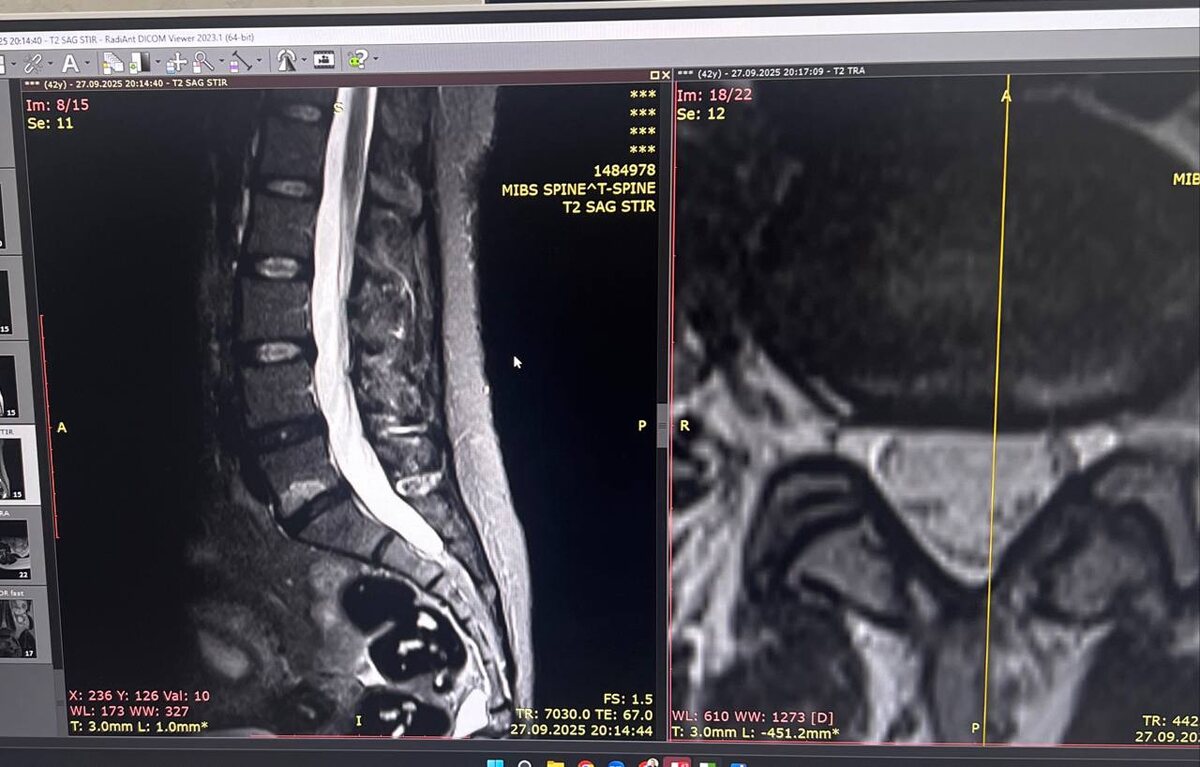

Когда МРТ показывает «воспаление» в позвонках, а врачи пожимают плечами

Modic 1 тип - это как пожар в подвале. Воспаление, отёк, всё горит. На МРТ это выглядит как яркое пятно - сигнал SOS от вашей кости.